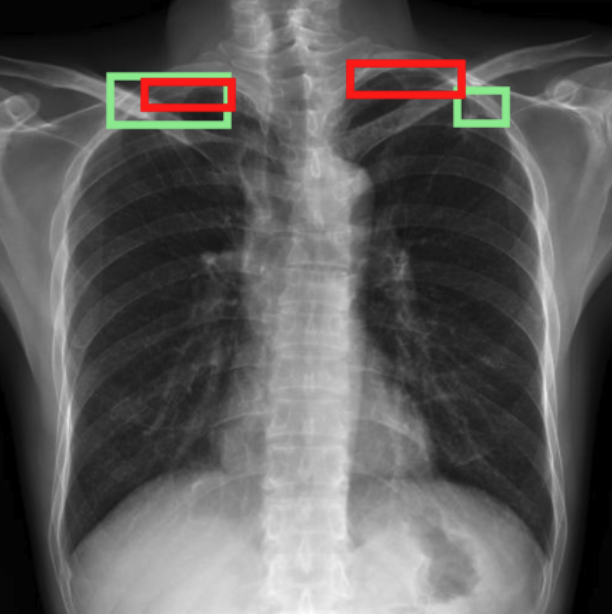

4.3.3 Visual grounding

In this section, we evaluate RadVLM’s visual grounding capabilities, which could help clinicians localize specific regions or pathologies on a CXR. This is particularly useful once a pathology has already been identified – either by a radiologist’s input or through our previously described AI tasks – since it allows one to pinpoint exactly where the abnormality appears on the image.

We report performance metrics for the three main grounding tasks RadVLM was trained on: anatomical grounding using the Chest Imagenome test set, abnormality grounding using the VinDr-CXR test set, and phrase grounding using the MS-CXR test set (Table 1). For each task, we use mean Average Precision (mAP) as our primary evaluation metric.

Our results show that RadVLM performs well at localizing anatomical regions (e.g., “right lung”, “aortic arch”, illustrated in Figure 5a), achieving a mAP of 85.8 %, by far surpassing the other CXR grounding models (Table 4). This advantage is partly explained by including the Chest Imagenome dataset (and thus the anatomical grounding task) in the training set, which CheXagent and MAIRA-2 did not leverage. However, it remains a key feature for any grounding model to possess a fine-grained understanding of CXR anatomy.

For the abnormality grounding task, RadVLM is less consistent (Figure 5b), likely due to higher sparsity of abnormality locations and labels, yet it still achieves best performance (Table 4). For the phrase grounding task, while MAIRA-2 and CheXagent demonstrate great performance, RadVLM surpasses them with a mAP of 81.8% (Table 4), presumably benefiting from the newly released PadChest-GR dataset (Castro et al.,, 2024) used for training.

Overall, these results show that our instruction tuning strategy for visual grounding (covering three essential tasks), combined to a modern VLM backbone, offers a promising avenue to help clinicians localize anatomical and pathological features during a CXR exam. Furthermore, providing fine-grained details within an LLM-generated output may also enhance the ability to answer grounded questions in a multi-turn setting, as we explore next.

a. Anatomical grounding

silhouette

junction

structures

lung

abdomen

mediastinum

arch

b. Abnormality grounding

thickening

fibrosis

enlargement

lung disease